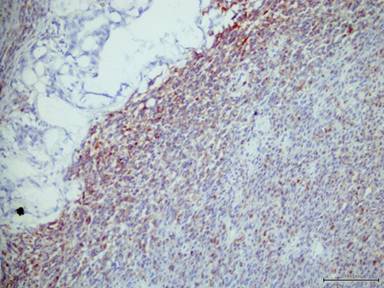

Immunohistochemistry was performed on an automated immunostainer by the avidin-biotin complex technique, using monoclonal antibodies to pan-cytokeratin, carcinoembryonic antigen, vimentin, smooth muscle actin (SMA), desmin, myogenin, CD68, CD117, S-100, CD34, p53, K-ras and Ki-67. We observed that the adenocarcinomatous component was positive for pan-cytokeratin and carcinoembryonic antigen (Figure 4). Both components were positive for p53 and K-ras, but they were negative for desmin, SMA, myogenin, CD68, CD117, S-100, and CD34. The Ki-67 proliferation index was 2%. The sarcomatous component exhibited diffuse immunoreactivity for vimentin (Figure 5) and focal immunoreactivity for SMA. Besides, two of sixteen peri-pancreatic lymph nodes showed a metastasis of the adenocarcinomatous component.

Figure 5. Vimentin was positive in sarcomatous component but negative in adenocarcinomatous component (adenocarcinomatous area is on the left of the figure). |